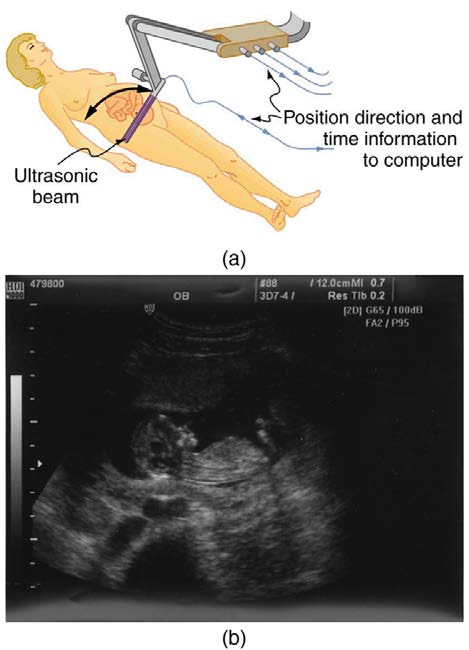

The most common ultrasound applications produce an image like that shown in Figure 17.45. The speaker-microphone broadcasts a directional

beam, sweeping the beam across the area of interest. This is accomplished by having multiple ultrasound sources in the probe’s head, which are

phased to interfere constructively in a given, adjustable direction. Echoes are measured as a function of position as well as depth. A computer

constructs an image that reveals the shape and density of internal structures.

index-619_1.jpg

index-619_2.jpg

CHAPTER 17 | PHYSICS OF HEARING 617

Figure 17.45 (a) An ultrasonic image is produced by sweeping the ultrasonic beam across the area of interest, in this case the woman’s abdomen. Data are recorded and

analyzed in a computer, providing a two-dimensional image. (b) Ultrasound image of 12-week-old fetus. (credit: Margaret W. Carruthers, Flickr)